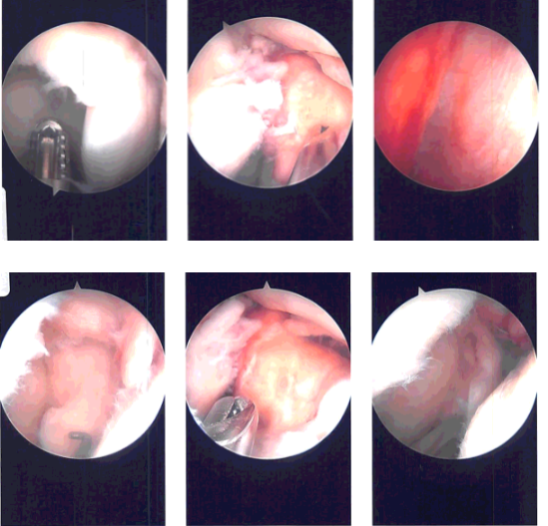

Intraoperative Arthroscopy Images

FlipCutter was used and drilled into the knee. Once the drill was inside the knee, it was flipped back and a 25-mm turnover was made. The reamer was again inserted back into the knee and flipped back to the normal position and retrieved out.

A FiberLink was inserted and retrieved. Similarly, a tibial tunnel was made using a tibial jig for the medial portal. A 60-degree angle was used. FlipCutter was used again to make a 30-mm tunnel in a similar fashion. A FiberLink was inserted and the suture was held on to each other.

Once the quadriceps tendon was ready, it was marked and inserted over the FiberLink on the femoral side and passed into the tunnel. Then, the tibial side was also passed to the tibial tunnel using the FiberLink.

Once the tendon was in place, it was tightened on either side and found to be in a good position. The graft was tightened over the tibial side and was tightened over the button along with two 4.7 size SwiveLock. The knee was cycled 30 times before final tightening.

The knee was thoroughly irrigated. The final pictures were taken and saved. The tendon was found to be in good tension. Notchplasty of the lateral femoral condyle was performed also. The final pictures were taken and saved. Tourniquet was released at this time.